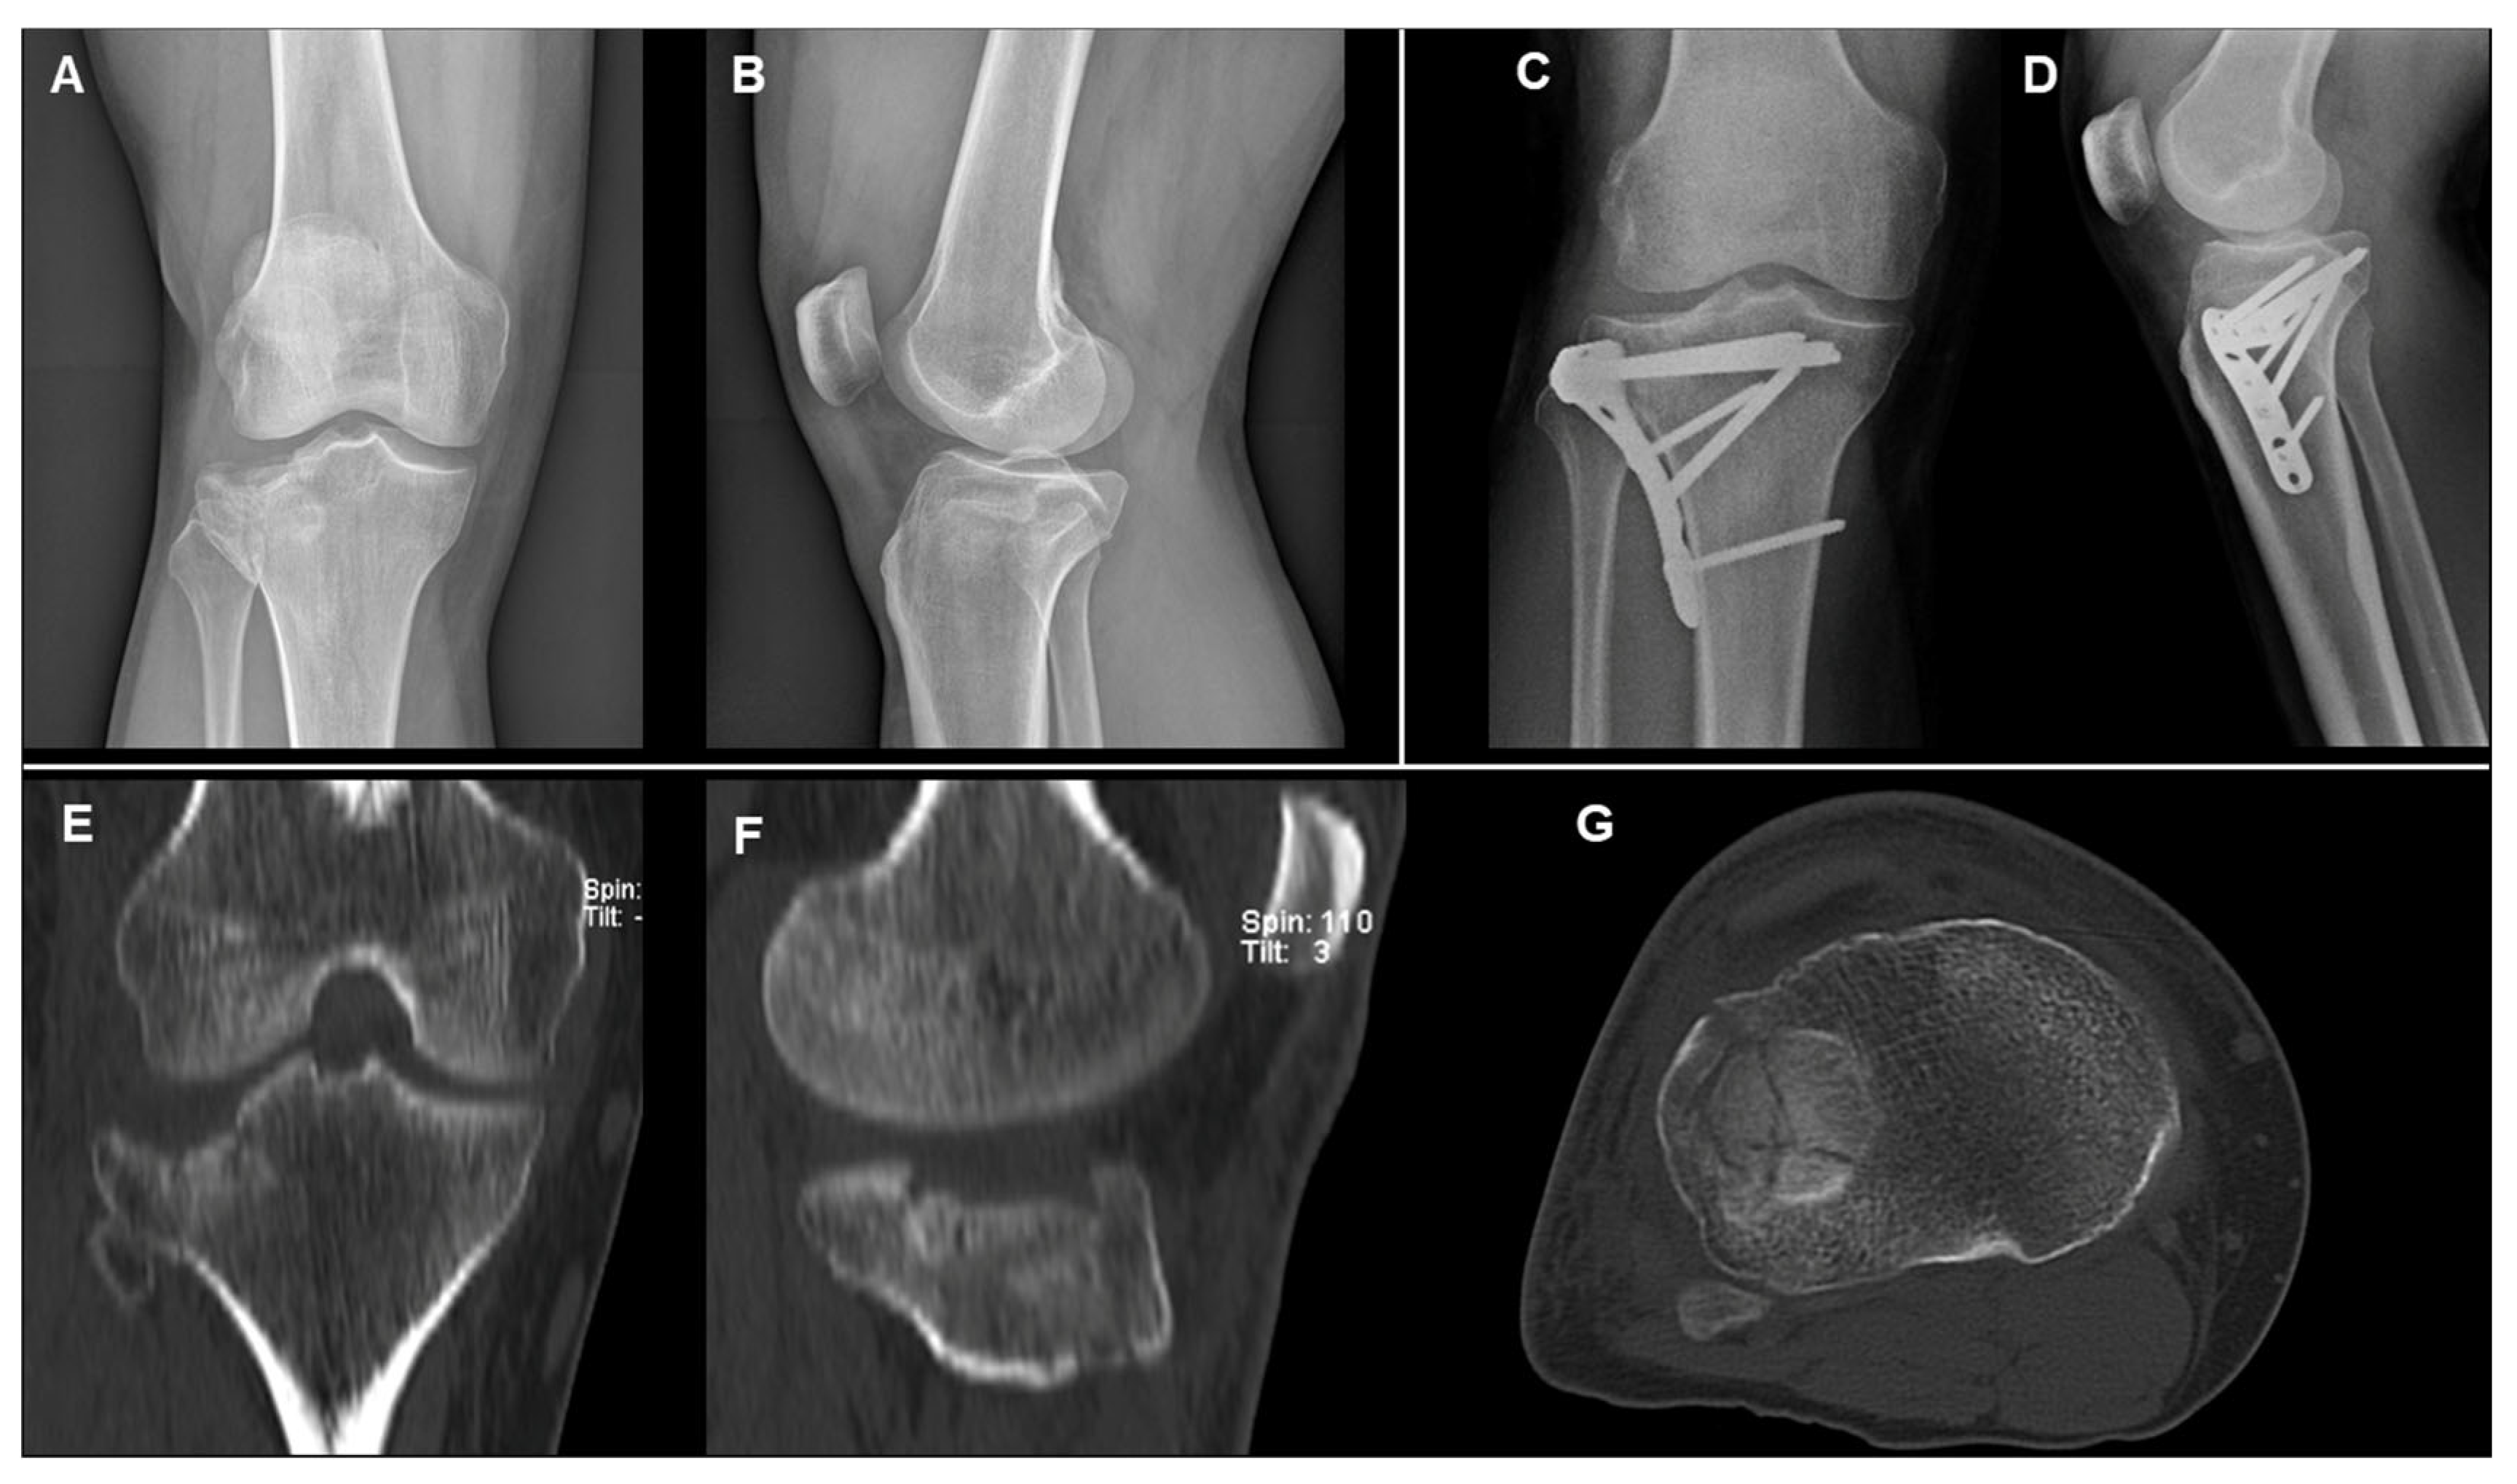

- MCFs (Schatzker II–IV): ORIF with a single lateral plate and screws for type II and III; medial plate and screws for type IV.

- BCFs (Schatzker V–VI): ORIF with two plates (medial and lateral) and screws.